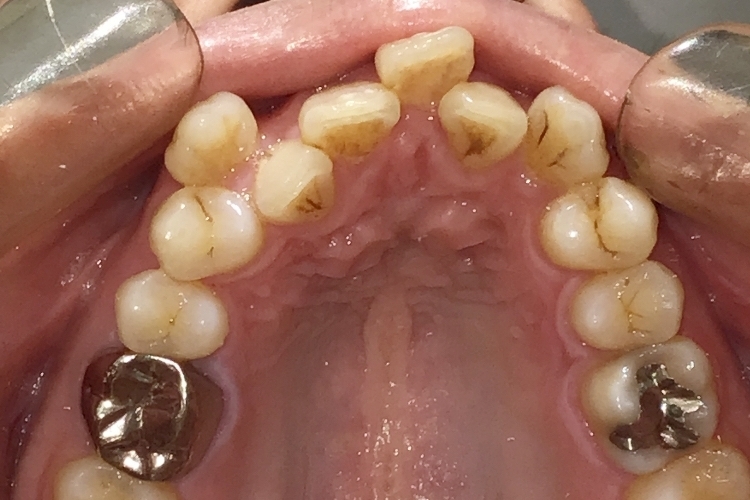

Before

浜松市中央区・自動車学校前駅のインビザラインの症例

K.M 20代女性

上の前歯が前方に出ていて横顔が気になるとの主訴でご来院。上下犬歯から犬歯までの6本が噛み合うよう、全体的に歯を内側に移動させることで、前歯の噛み合わせを整え叢生と開咬を治療しました。

​治療の期間:R5. 7/5〜R7. 1/17

​治療の価格:66万円